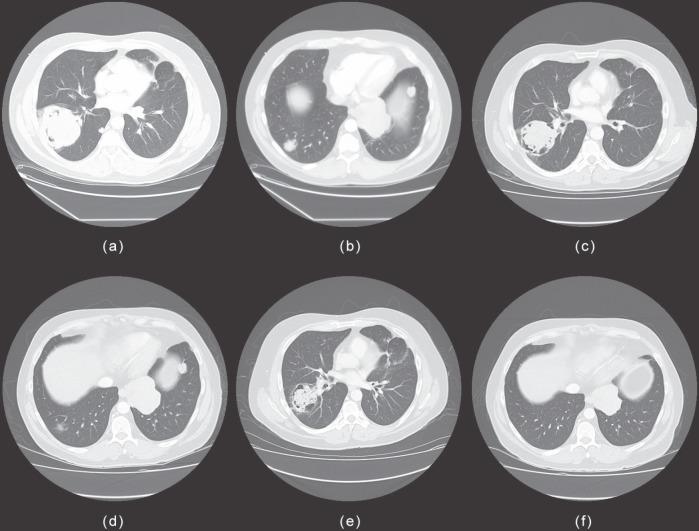

We describe a case of recurrent metastatic malignant ameloblastoma to the lungs with hypercalcaemia in a 47-year-old man. The first lung metastasis was resected nine years after the initial primary, and the tumour recurred with extensive pulmonary metastases 21 years after the primary tumour was resected. This case presented with malignancy-associated hypercalcaemia, likely due to paraneoplastic syndrome, which is exceedingly unusual in association with malignant ameloblastoma. He was successfully treated with carboplatin/paclitaxel and showed the longest survival and stable disease, from the diagnosis of recurrent metastasis, recorded as a case report. This regimen is reasonably well tolerated and can be repeated safely.

我们报告一例47岁男性复发性转移性恶性成釉细胞瘤伴高钙血症至肺部的病例。首次肺转移在原发肿瘤初次切除9年后被切除,原发肿瘤切除21年后肿瘤复发并伴有广泛的肺转移。该病例出现了与恶性肿瘤相关的高钙血症,可能是由于副肿瘤综合征,这在恶性成釉细胞瘤中极为罕见。他接受卡铂/紫杉醇治疗成功,从复发性转移诊断起显示出最长的生存期和疾病稳定,作为病例报告记录在案。该方案耐受性良好,可以安全重复使用。